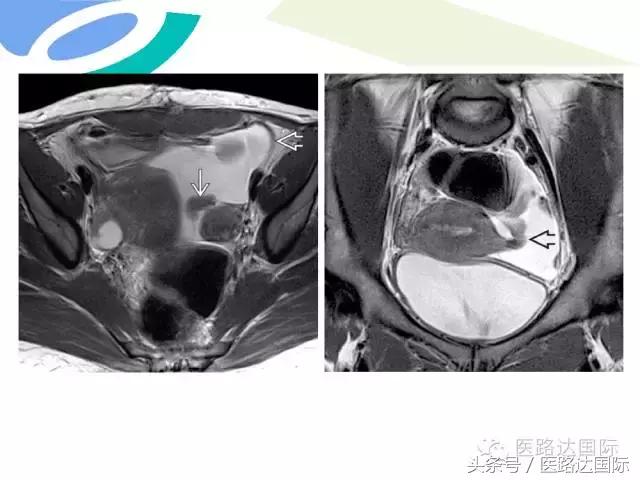

首都医科大学附属北京妇产医院梁宇霆教授从流行病学、临床特点、实验室检查、病理改变、影像学特点及治疗与预后六个方面向我们详细地介绍了女性生殖系统结核;并且着重介绍了子宫输卵管造影(HSG)的作用。在最后,梁教授还向大家介绍了如何鉴别诊断女性生殖系统结核、盆腔炎性病变和卵巢癌。

女性生殖系统结核的影像诊断及鉴别